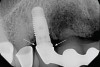

Implant mobility is not a useful diagnostic parameter. If an implant is mobile, it should be considered failed and removed. Conversely, implants may have advanced peri-implantitis with bone loss from 50% to 90% of implant length and still exhibit no mobility when examined clinically (Figure 1).

Figure 1  An implant, 12 mm in length, with advanced peri-implantitis and 10-mm bone loss, exhibiting no mobility.

Figure 1